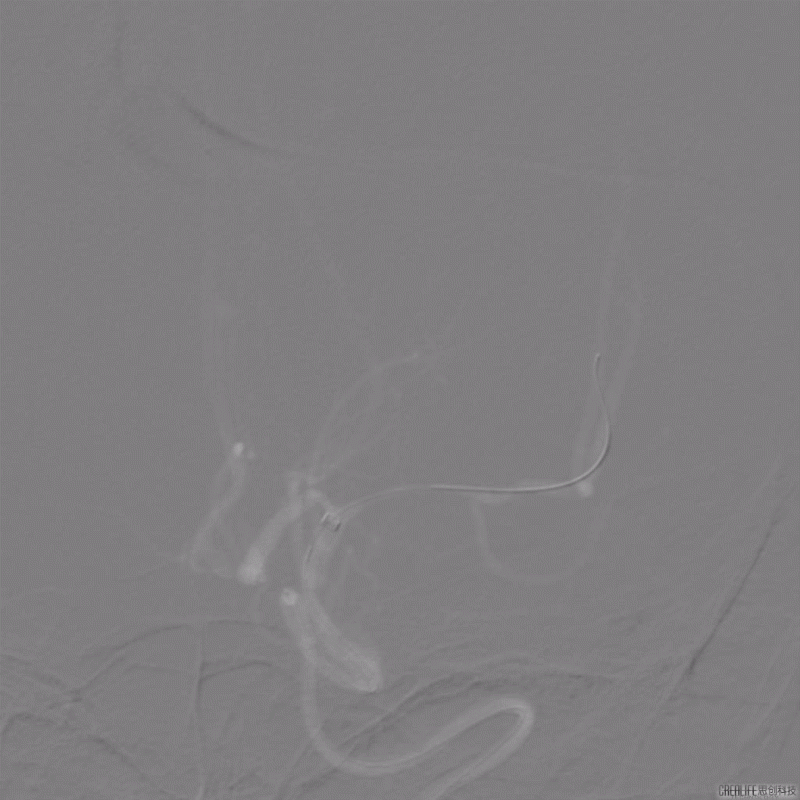

支架释放。

导丝怎么扩【载药时代 球扩天下】NOVA DES®颅内药物洗脱支架在颅内富穿支区域使用体会二例!_https://www.jmylbn.com_新闻资讯_第20张

导丝怎么扩【载药时代 球扩天下】NOVA DES®颅内药物洗脱支架在颅内富穿支区域使用体会二例!_https://www.jmylbn.com_新闻资讯_第21张

术后影像及检查

此例病人术后第2天言语功能完全恢复,术后第3天,右手功能有所恢复,术后1周右上肢功能完全恢复。

影像结论:左侧大脑中动脉完全开通,达3级再通。